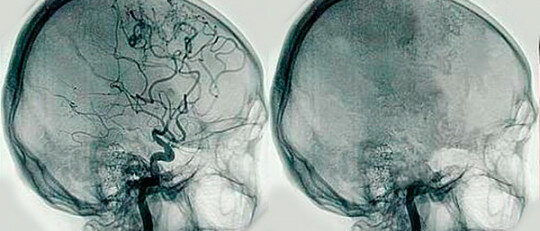

Con la técnica de Seldinger hizo que el proceso fuera mas seguro. Esta técnica produjo un gran avance en la radiología intervencionista. Con la técnica de Seldinger hizo que el proceso fuera mas seguro. Esta técnica produjo un gran avance en la radiología intervencionista.

Esta técnica consiste en la punción directa vascular u orgánica mediante una aguja. Gracias a esto se realizaron procedimientos diagnósticos y terapéuticos mínimamente invasivos. Esta técnica consiste en la punción directa vascular u orgánica mediante una aguja. Gracias a esto se realizaron procedimientos diagnósticos y terapéuticos mínimamente invasivos.

La angiografía digital ha mejorado el estudio y tratamiento de las patologías vasculares. La angiografía digital ha mejorado el estudio y tratamiento de las patologías vasculares.